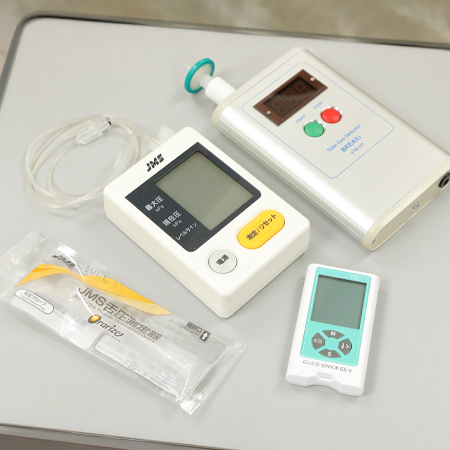

口臭検査機と口腔機能検査機

気になる口臭を数値で診断いたします。その他、舌圧、咀嚼能率などのお口の様々な検査を実施いたします。